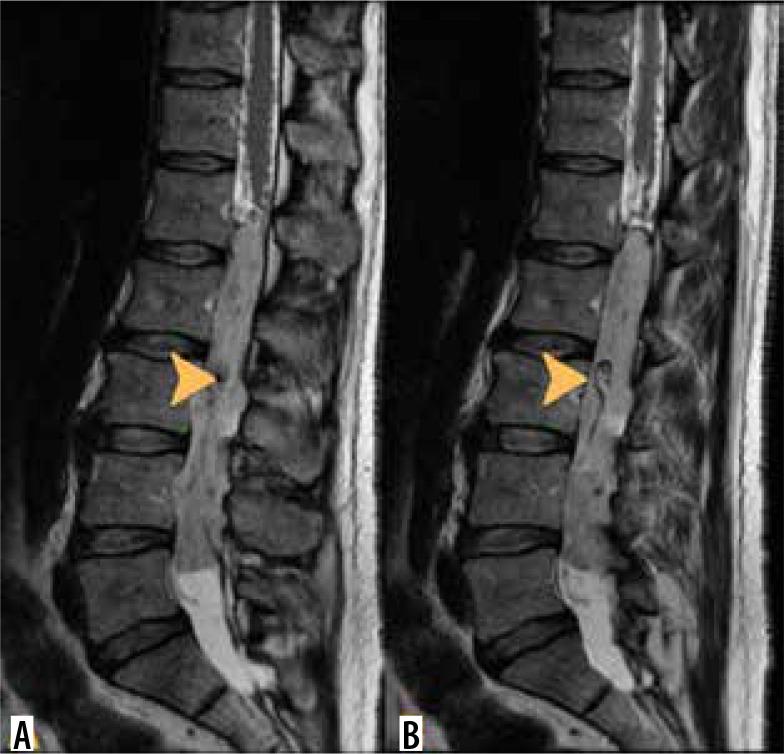

脊髓髓内肿瘤的影像学检查

Imaging of intramedullary tumours of the spinal cord.

Intramedullary tumours (IMTs) are the least common neoplasms of the spinal canal. The majority of them are ependymomas and astrocytomas, the third commonest is haemangioblastoma, while other tumours of the spinal cord are relatively rare. This review presents on update on the imaging of spinal cord tumours. Magnetic resonance imaging (MRI) is the imaging method of choice in diagnosing IMTs, with other modalities playing a supplementary role. The authors discuss the MRI protocol in IMTs including advanced techniques and present the imaging features of particular tumours. The differentiation of IMTs from other spinal cord diseases is also presented.

摘要

髓内肿瘤(IMTs)是椎管内最不常见的肿瘤。其中大多数是室管膜瘤和星形细胞瘤,第三常见的是血管母细胞瘤,而脊髓的其他肿瘤相对少见。本综述介绍了脊髓肿瘤成像的最新情况。磁共振成像(MRI)是诊断IMTs的首选成像方法,其他方式起辅助作用。作者讨论了IMTs的MRI检查方案,包括先进技术,并介绍了特定肿瘤的成像特征。还介绍了IMTs与其他脊髓疾病的鉴别诊断。